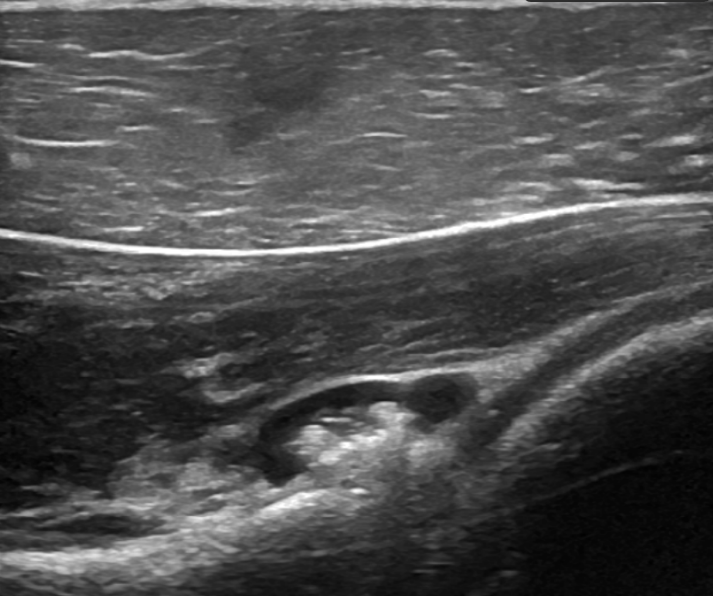

Posterior glenoid labral tear